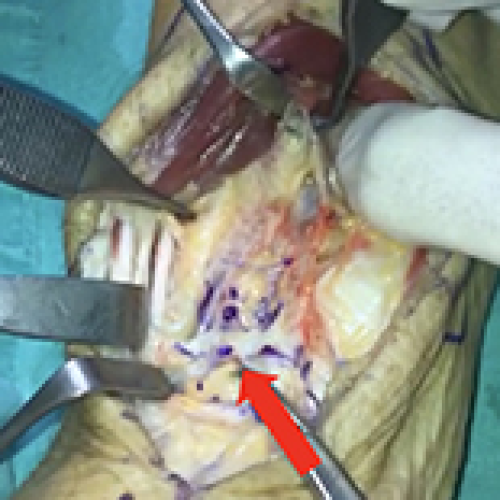

Treatment of AVN-Induced Proximal Pole Scaphoid Nonunion Using a Fifth and Fourth Extensor Compartmental Artery as a Vascularized Pedicle Bone Graft: A Retrospective Case Series

19 May 2024 : Clinical Research

Müjdat Adaş

DOI: 10.12659/MSM.944553

Med Sci Monit 2024; 30:e944553

5,022